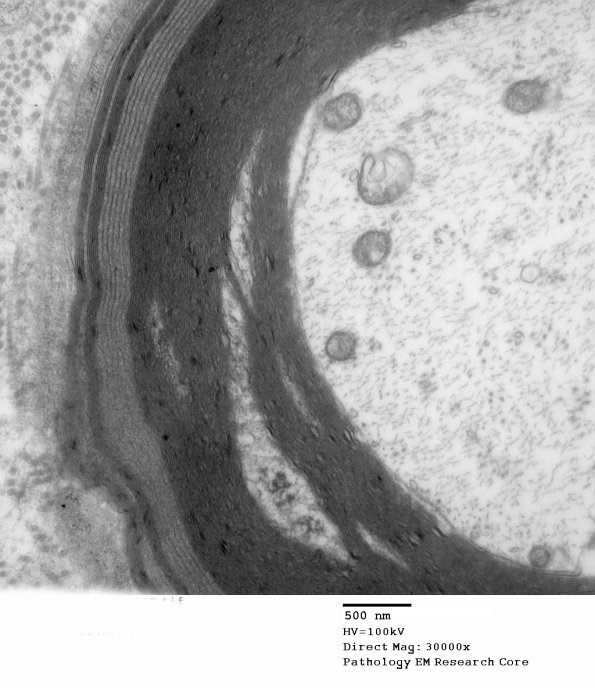

In this axon the higher magnification images show the delicate major dense lines are harder to decipher when they are cut more tangentially. (electron micrograph)